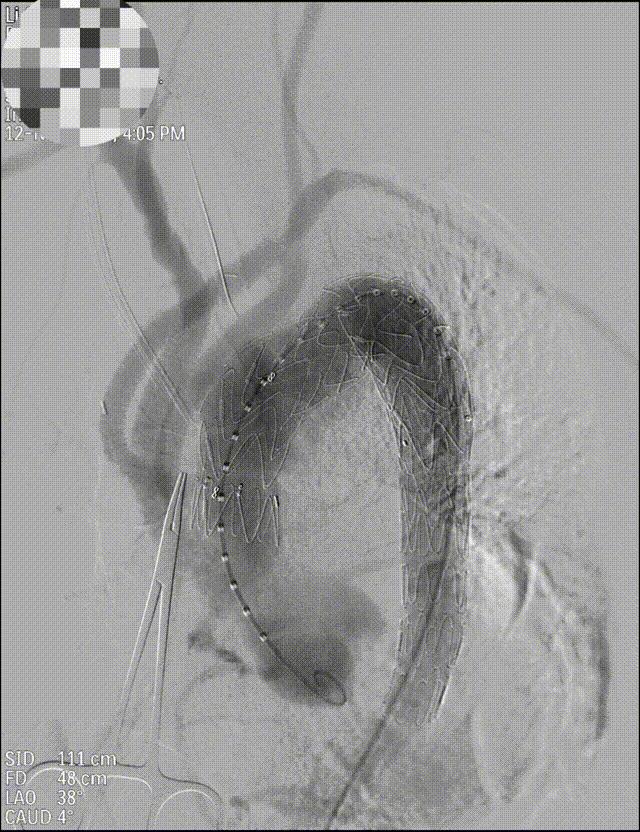

Ⅰ型主动脉夹层:正中开胸深低温停循环手术——升主动脉人工血管置换+主动脉弓人工血管置换+降主动脉支架置入术(孙氏手术);正中开胸体外循环——升主动脉人工血管置换+主动脉弓人工血管置换+介入胸主动脉支架置入术(一站式杂交手术)

人工血管+介入支架,杂交手术